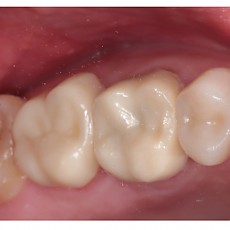

시술전후사진 12 페이지

Total 189건 12 페이지